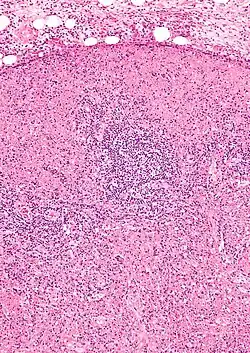

Choroba Kikuchi-Fujimoto jest bardzo rzadka; przypadki opisywano na całym świecie, częściej w populacji japońskiej. Obraz kliniczny, histopatologia i cechy immunohistochemiczne sugerują etiologię wirusową schorzenia, ale jak dotąd nie udowodniono tej hipotezy[3]. Rozpoznanie stawiane jest zazwyczaj na podstawie wyniku biopsji powiększonych węzłów szyjnych. Choroba spontanicznie ustępuje w przeciągu 1-4 miesięcy[1]. Chorobę opisali, niezależnie od siebie, Masahiro Kikuchi i Y. Fujimoto w 1972 roku.